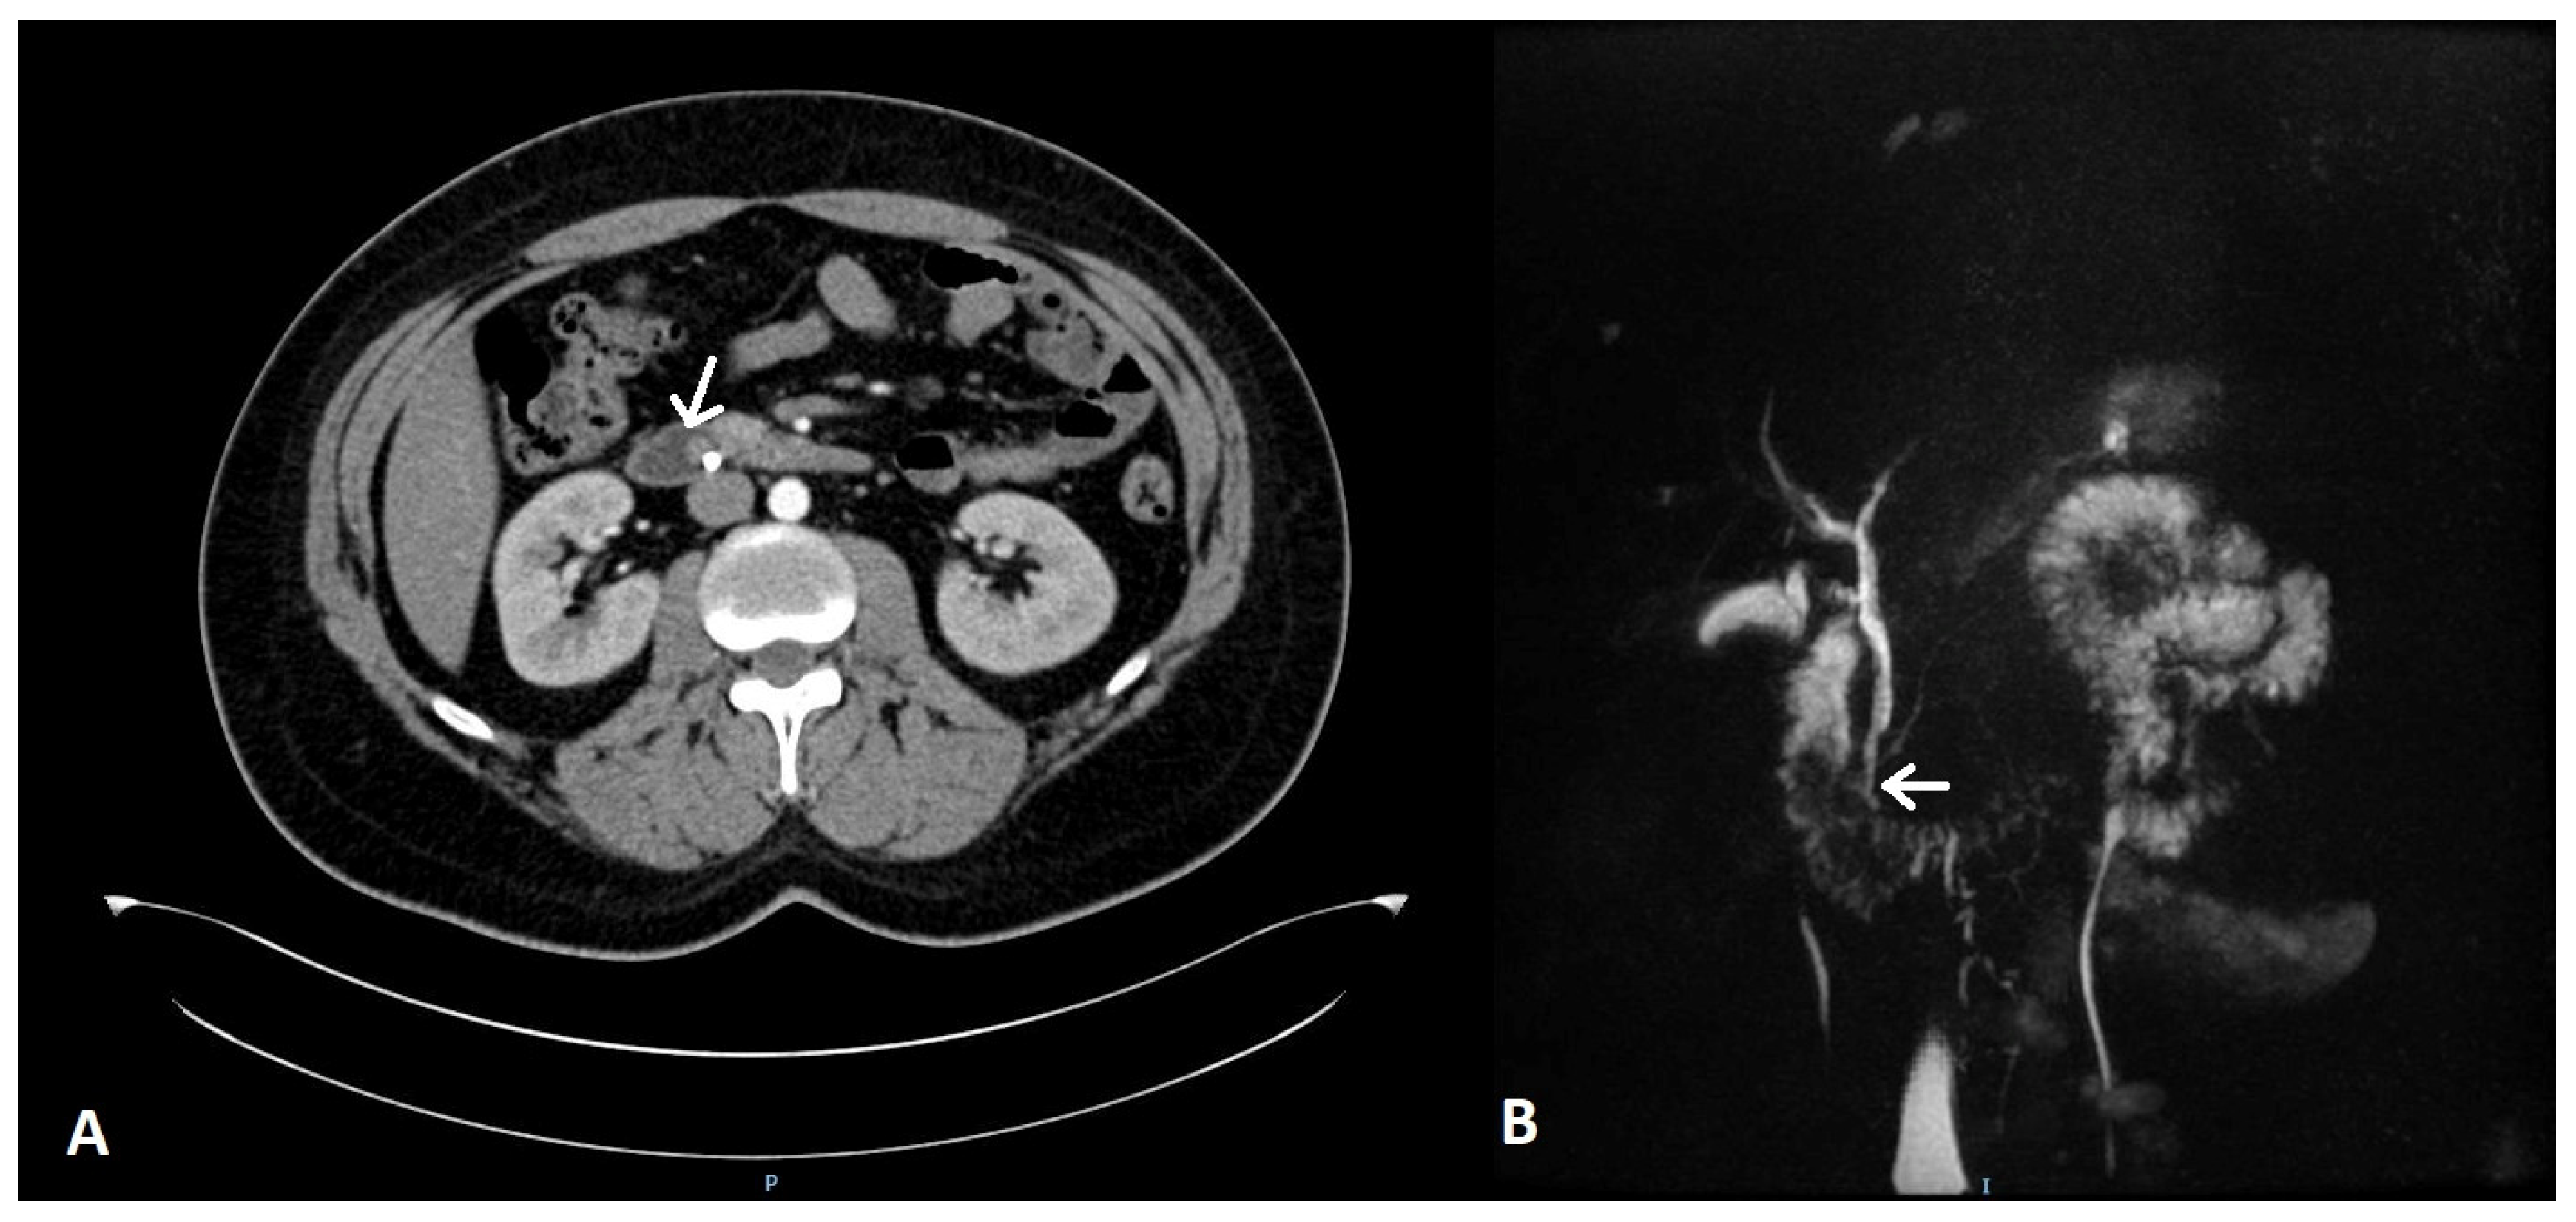

2. Case Report 1

3. Case Report 2

4. Case Report 3